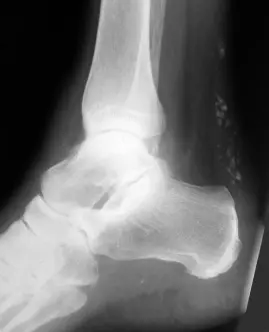

Achilles Tendinitis

Overview

Achilles tendinitis is a condition characterized by inflammation of the Achilles tendon.

Workup for Achilles Tendonitis

- A clinical diagnosis

- X-ray:

- may show calcification around the tendon